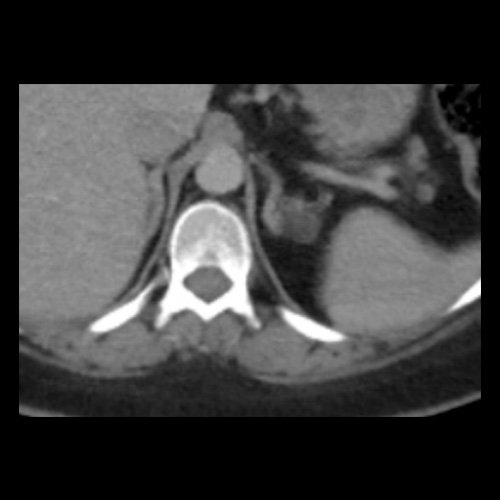

TC de abdomen y pelvis con contraste endovenoso (12/02/2026) Corte axial: adenoma adrenal izquierdo de 16 mm.

Tomografía de abdomen y pelvis sin contraste oral con contraste EV (12/02/26): El hígado es de forma, tamaño y situación habituales. Su superficie es lisa, y sus bordes son agudos. Imagen hipovascular aislada de 15 mm en segmento V de aspecto inespecífico. Sugiero complementar con RMI. La vía biliar intra y extrahepática es de calibre conservado. La vesícula biliar es de forma, tamaño y situación normales, sin imágenes que sugieran la presencia de litiasis. Tener en cuenta que este método puede pasar por alto litiasis colesterínicas. El bazo es de forma, tamaño y situación normales. El páncreas es de características normales. El conducto de Wirsung es de calibre conservado. Adenoma adrenal izquierdo de 16 mm. Ambos riñones son de forma, tamaño y situación habituales. Concentran y eliminan adecuadamente la sustancia de contraste. Sin evidencia de alteraciones calicopiélicas ni ureterales. La aorta, las arterias ilíacas primitivas, internas, externas y femorales, son de calibre y trayecto conservado, permeables. La vena cava inferior y las venas ilíacas primitivas, internas, externas y femorales son de calibre y trayectoria conservados, permeables. No se observan adenomegalias intraperitoneales, retroperitoneales, ilíacas ni inguinales. No se observan alteraciones a nivel del tracto gastrointestinal. La vejiga es de paredes lisas, sin presentar efectos de masa endoluminales ni parietales. Utero en AVF, lateralizado a izquierda. Pequeña hernia umbilical de contenido graso y escaso líquido intrasacro. No se identifican alteraciones en las estructuras óseas visualizadas.